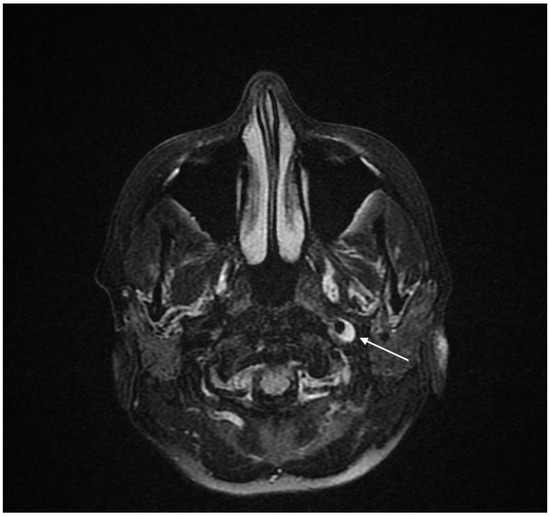

Spontaneous Multiple Cervical Artery Dissections Detected with High-Resolution MRI: A Prospective, Case-Series Study

Background: Cervical artery dissection (CAD) is a leading cause of acute ischemic stroke among young and middle-aged patients. Currently, the growing availability of high-resolution magnetic resonance imaging (MRI), particularly fat-saturated T1-weighted black-blood SPACE sequences, allows the non-invasive, rapid, and reliable diagnosis of multiple arterial dissections. Methods: We reported our experience from two tertiary stroke centers of patients diagnosed with spontaneous multiple cervical artery dissections, detected with high-resolution MRI, during a three-year period (2022–2025). Results: Among 95 consecutive patients with CAD, 11 patients (mean age: 48 ± 9 years, 6 (55%) females) were diagnosed with multiple symptomatic or asymptomatic CADs, whereas in 84 patients (mean age: 49 ± 11 years, 32 (38%) females) a single CAD was detected. In all patients, high-resolution MRI and MR-angiography were performed, whereas digital subtraction angiography (DSA) with simultaneous evaluation of renal arteries was conducted in nine patients. A history of trauma or chiropractic manipulations, intense physical exercise prior to symptom onset, recent influenza-like illness, and recent childbirth in a young female patient were reported as predisposing risk factors. Cervicocranial pain, cerebral infarctions leading to focal neurological signs, and Horner’s syndrome were among the most commonly documented symptoms. Characteristic findings in the high-resolution 3D T1 SPACE sequence were detected in all patients. Fibromuscular dysplasia and Eagle syndrome were detected in four patients and one patient, respectively. Eight patients were treated with antiplatelets, whereas three patients received anticoagulation with low-molecular-weight heparin. There was only one case of stroke recurrence during a mean follow-up period of 9 ± 4 months. Conclusions: This case series highlights the utility of specific high-resolution MRI sequences as a very promising method for detecting multiple CADs in young patients. The systematic use of these sequences could enhance the sensitivity of detecting multiple cervical CADs, affecting also the thorough investigation for underlying connective tissue vasculopathies, stratifying the risk for first-ever or recurrent ischemic stroke, and influencing acute reperfusion and secondary prevention therapeutic strategies. Full article

Figure 1